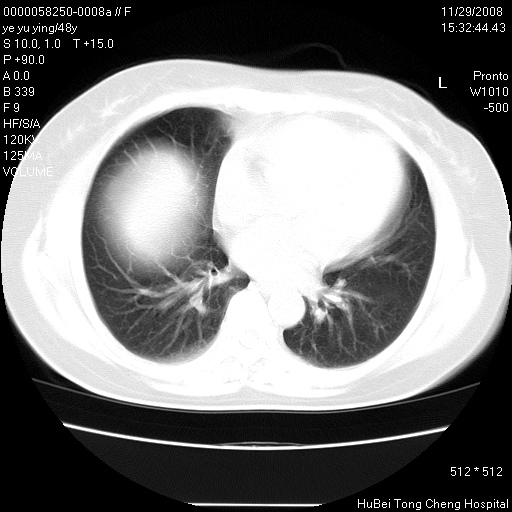

以下是引用zsl6918在2008-11-29 21:47:00的发言:[br]恶性肿瘤病史,转移瘤首先考虑。脂肪肝,胆囊结石。

以下是引用huenhao在2008-11-29 22:11:00的发言:[br]脂肪肝,胆囊结石。左肺病灶建议定期复查。

以下是引用liuyue在2008-11-30 5:44:00的发言:[br]1.左肺病变,首先考虑感染性病变,转移待排;建议治疗后复查。[br]2.肝脏密度普遍减低,考虑与化疗有关。[br]3.胆囊结石.